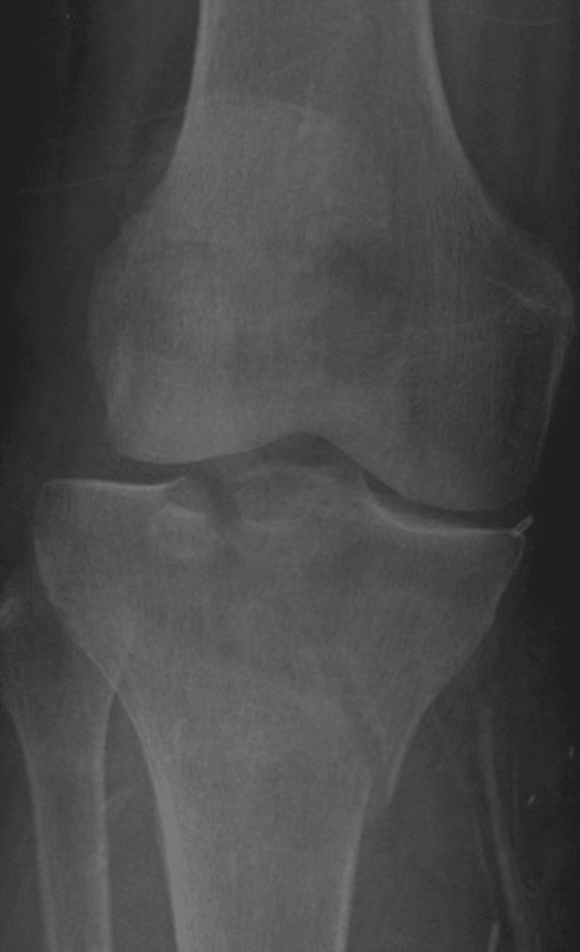

How would you grade this fracture based on the Schatzker classification system?

This is a medial tibial plateau fracture, this would be a type IV.